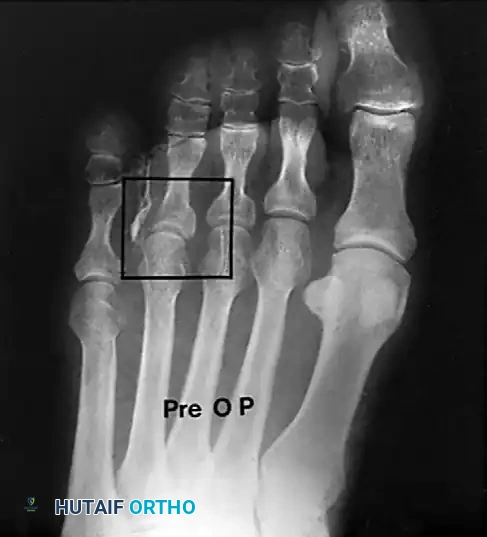

The development of lesser metatarsal callosities is frequently a secondary manifestation of first ray pathology. Hallux valgus deformity compromises the weight-bearing capacity of the first metatarsophalangeal (MTP) joint, leading to transfer metatarsalgia and subsequent hyperkeratosis beneath the lesser metatarsal heads.

As demonstrated in landmark studies by Lee et al., over 90% of patients with lesser metatarsal callosities experience significant improvement of their pain following the anatomical correction of a concomitant hallux valgus deformity.

Surgical Warning: Although symptoms associated with lesser metatarsal callosities may improve following first ray realignment, any fixed deformity of the lesser toe at the MTP joint must be corrected concurrently at the time of hallux valgus correction to obtain complete, long-term symptomatic relief.

These lesions are almost exclusively located beneath the lesser metatarsal heads, most commonly the second or third. They are the direct result of a prominent plantar condyle of the metatarsal head driving into the plantar fat pad during the stance phase of gait.

If the entire metatarsal is excessively long or plantarflexed, a Weil osteotomy is preferred to elevate and shorten the metatarsal head, thereby globally offloading the keratotic lesion.